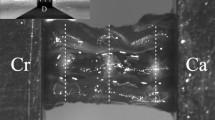

Slides containing multifidus muscle from L2 (non-IDD) and L4 (IDD) were incubated in running water for 2 min, Weigert’s haematoxylin for 10 min and Van Gieson’s solution for 1 min before dehydration and mounting. Slides were imaged (ImageScope, Leica), and thickness of the connective tissue separating the multifidus and adjacent longissimus muscles was measured (Fig. 2b) (ImageJ software, NIH).

Connective tissue (CT) separating the multifidus and longissimus muscles (epimysium) was significantly thicker in L4 multifidus (high-IDD group) than at L2 (low-IDD group; Table 2, Fig. 3). Long-term exposure to physical activity reduced CT thickness in both SPARC-null and WT mice (Table 2, Fig. 3). Immunofluorescence staining for Col-I showed limited expression in the epimysium, and IDD or PA did not affect the area of Col-I as a percentage of the multifidus (Table 2, Fig. 3).

Histological analysis of fibrosis in the multifidus muscle of SPARC-null animals. Connective tissue thickness and the percentage of multifidus positive for Col-1 expression were measured in the low IDD (SPARC “Y”, IDD “Low”), high IDD (SPARC “Y”, IDD “High”) and wild-type (SPARC “N”, IDD “WT”) mice that were sedentary (Exercise “Sed”) or physically active (Exercise “PA”). Data are presented as mean + SEM